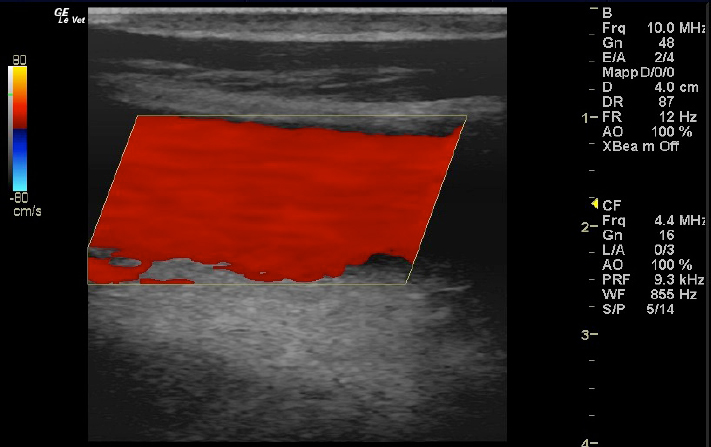

The left jugular vein appeared as an anechoic tubular structure which collapsed under the probe pressure, the color Doppler examination revealed normal blood flow within the vessel (Fig. 3). Bi-dimensional ultrasonography of the right jugular vein showed a heterogeneous, non-cavitating, hypoechoic structure occluding a narrowed right jugular vein for about 30 cm of length localized in the proximal and mid-portion of the neck compatible with a thrombus (Fig. 4). The color Doppler examination showed blood flow through the lateral portions of the thrombus in the cranial and mid-portions of the right jugular vein (Fig. 5). Cranially to the thrombus, a marked distension of the maxillary and linguofacial veins was evident, with a turbulent and echogenic flow; the latter was compatible with blood stasis near the thrombus (Fig. 6). Caudally to the thrombus, the right jugular vein presented reduced diameter, thickened walls, and normal blood flow (Fig. 7). The cranial part of the thrombus originated from a heterogeneous scare tissue, localized at the level of the right mandibular angle (Fig. 8). After injection of the first saline contrast bolus in a right facial vein, no microbubbles appeared in the right jugular vein, caudally to the thrombus, proving the presence of a complete right jugular vein occlusion. On the contrary, after injection of the second bolus, microbubbles were visualized in the left jugular vein as small, intense, echo signals within the vein lumen, demonstrating the presence of collateral circulation that drained the blood from the right facial veins to the left jugular vein (Fig. 9). Venography results confirmed the complete occlusion of the right jugular vein and the presence of submandibular venous collaterals that connected the right facial veins with the left jugular vein (Figs. 10 and 11). Based on the previous results, the diagnosis of JVT with complete occlusion of the vessel lumen was confirmed. The horse’s owner refused any proposed medical or surgical therapy.

Fig. 3. Color Doppler image of the normal blood flow in the left jugular vein.